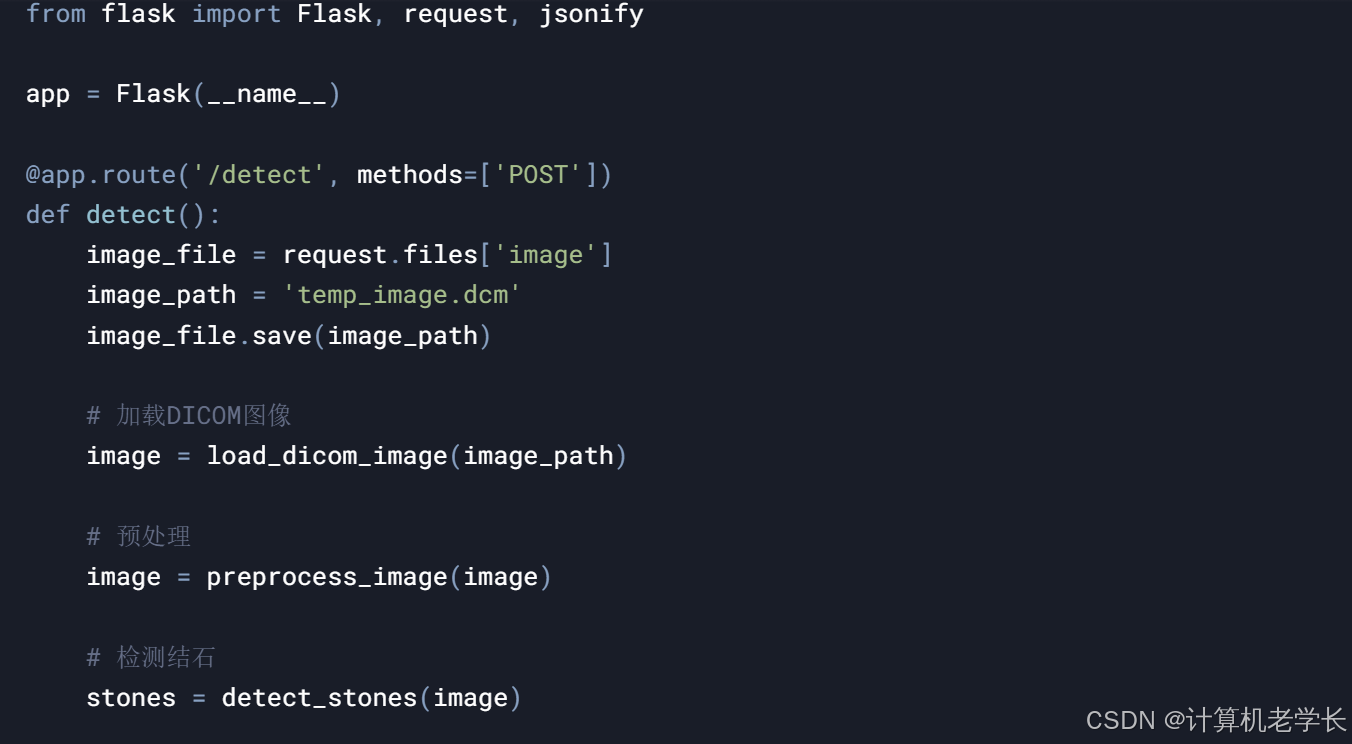

四、系统实现

4.1 数据采集

4.2 数据预处理

4.3 结石检测

4.4 结果可视化

4.5 系统管理